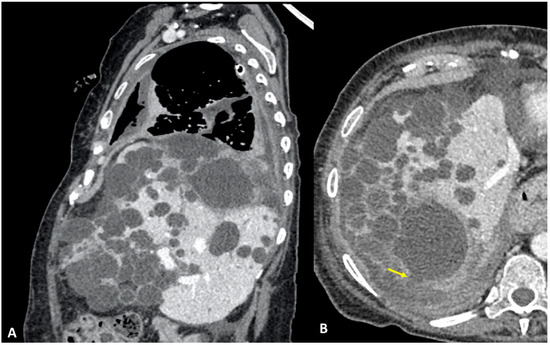

3.4. Case #4: Pancreaticopleural Fistula

4. Results and Discussion